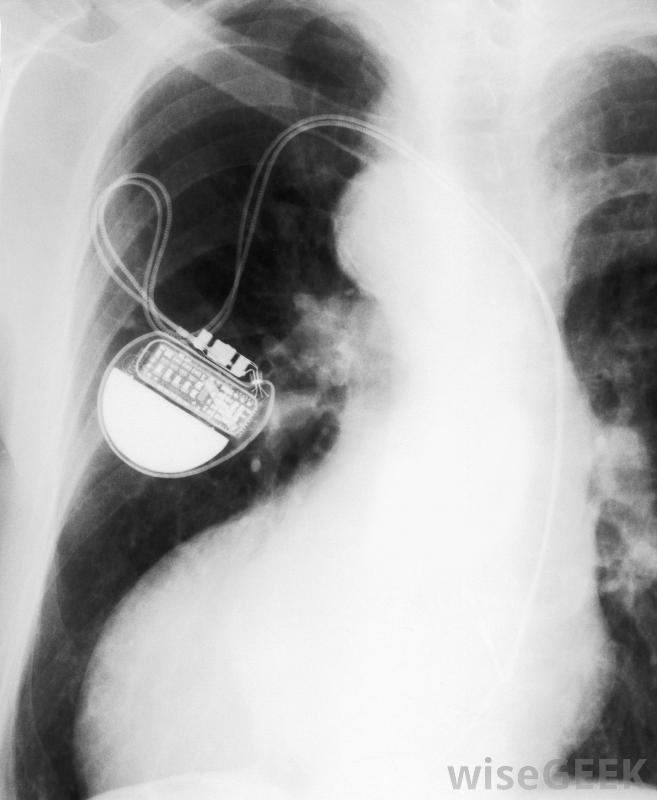

心律失常的患者需要起搏器的幫助。這些小裝置被植入人體最重要的器官之一心臟附近。因此,諸如起搏器植入和可能的起搏器修復等問題通常需要特別關注。

有起搏器的人應該定期檢查心率。心律失常的患者需要起搏器的幫助。這些小裝置被植入人體最重要的器官之一心臟附近。因此,諸如起搏器植入和可能的起搏器修復等問題通常需要特別關注。